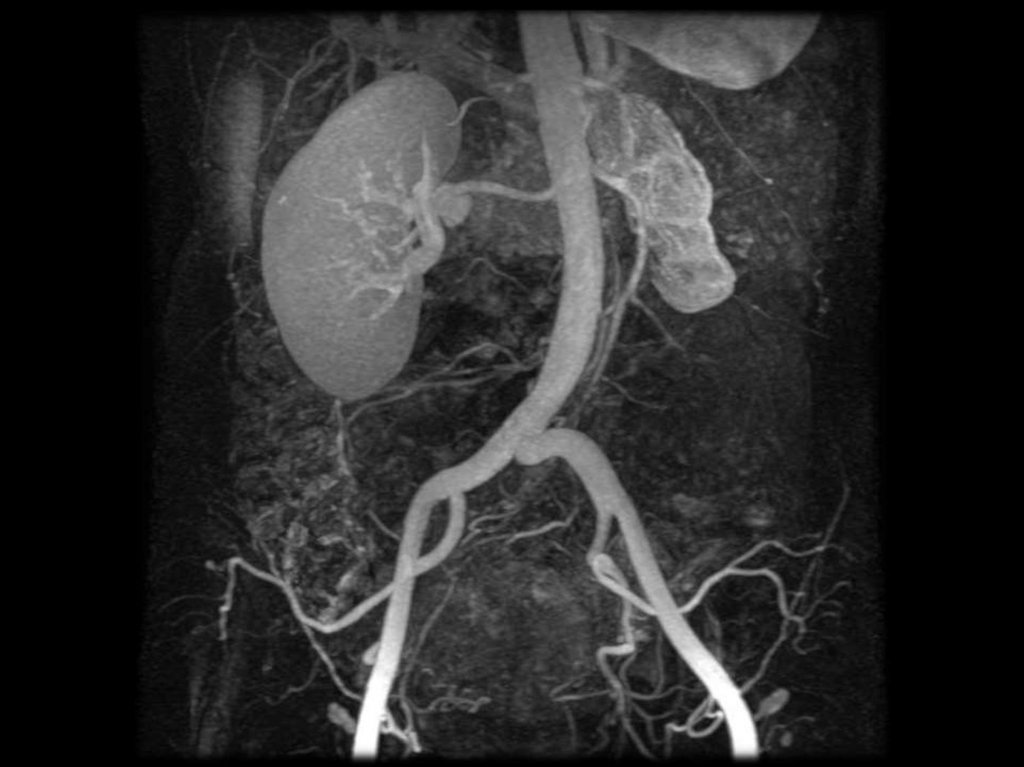

ПОЧЕЧНАЯ АНГИОГРАФИЯ

• требует трансфеморальной

артериальной катетеризации по

Сельдингеру.

• для определения количества и типа

ветвления магистральных артерий

выполняют

общую

обзорную

аортографию с установкой катетера на

уровне XII грудного позвонка

• Затем с учетом этих данных для

получения детального изображения

сосудистой системы каждой почки в

отдельности проводят селективное

исследование с введением катетера

поочередно непосредственно в одну

и другую почечную артерию.

• После

быстрого

введения

автоматическим

инъектором

водорастворимого РКС производят

серию снимков.